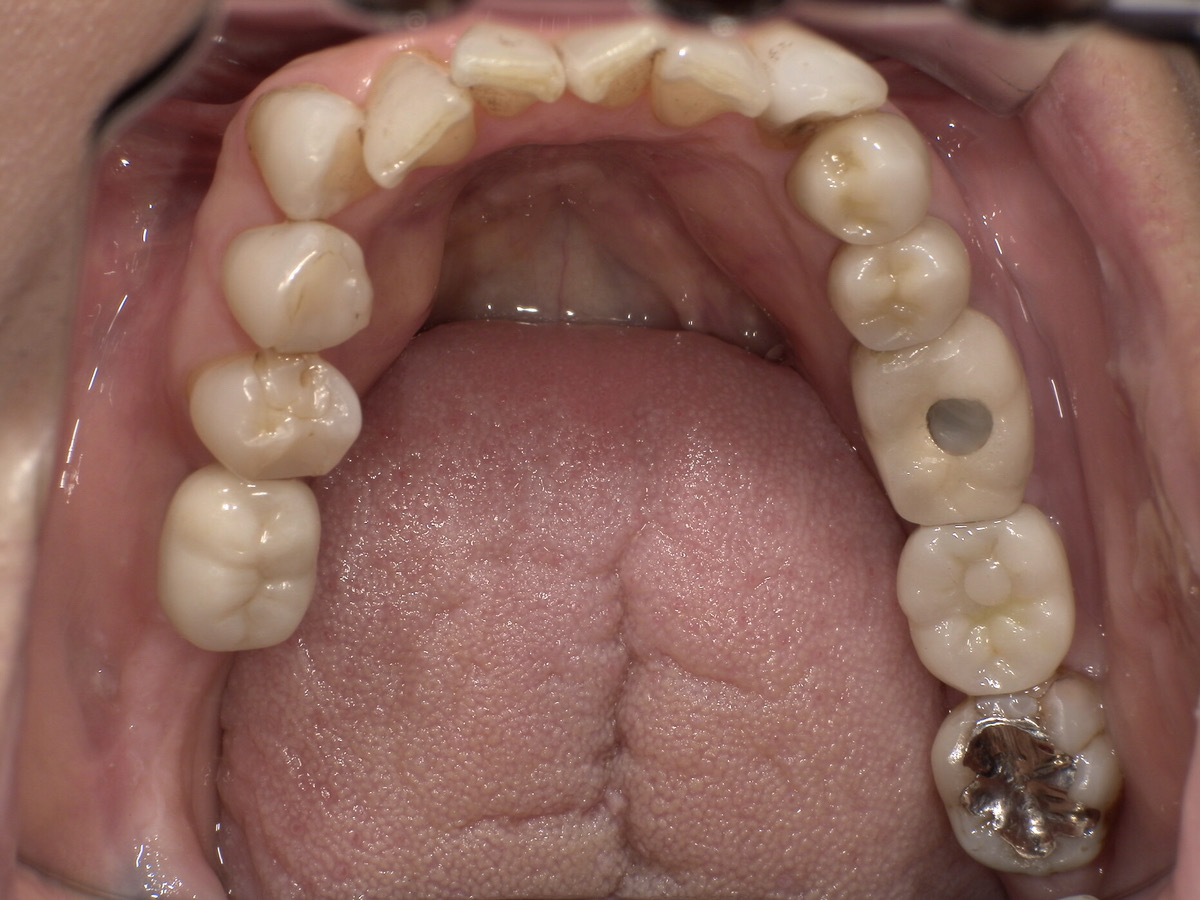

CASE 03

Before

After

施術内容左右下顎の第一・第二大臼歯の銀歯(被せ物)をジルコニアクラウンに交換。右下第二小臼歯の銀歯(詰め物)をジルコニアインレーに交換。

治療期間3か月

リスク・副作用ジルコニアは非常に強度が高いですが、強い衝撃や極端に強い噛み合わせ、歯ぎしり・食いしばりなどがある場合、まれに割れたり欠けたりする可能性があります。

費用 454,400円

※表示金額は全て税込みです。